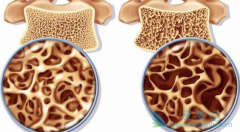

• 多发性骨髓瘤药物万珂(Velcade)有治疗骨质疏松的潜能

多发性骨髓瘤药物万珂(Velcade)有治疗骨质疏松的潜能

一治疗骨髓肿瘤的药物可能对骨质疏松有效,通过刺激干细胞实现。他们发现Millennium Pharmaceuticals公司生产的 Velcade (万珂)可刺激干细胞分化为骨组织。来自Massachusetts General医院和哈佛干细胞研究所的研究团队在JCI上报道:老鼠实验表明该药物 ...